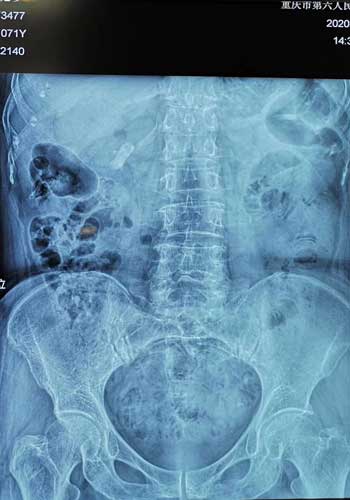

术前患者腹部平片所示膀胱内巨大结石。院方供图

“在详细询问患者的病史后,我们认为患者膀胱内巨大结石的形成可能与她既往发生脑梗导致神经源性下尿路功能障碍及长期的膀胱慢性感染有关。而且我们检查发现这颗巨大的结石已经占据了患者膀胱的大部分容积,所以导致患者出现了尿频、尿急、漏尿等症状,严重影响了患者的生存质量。同时,这个巨大结石对膀胱壁有着直接压迫作用,可能造成膀胱壁缺血坏死,甚至自发性破裂,后果不堪设想,必须马上进行手术。”泌尿外科主任靳文生解释道。